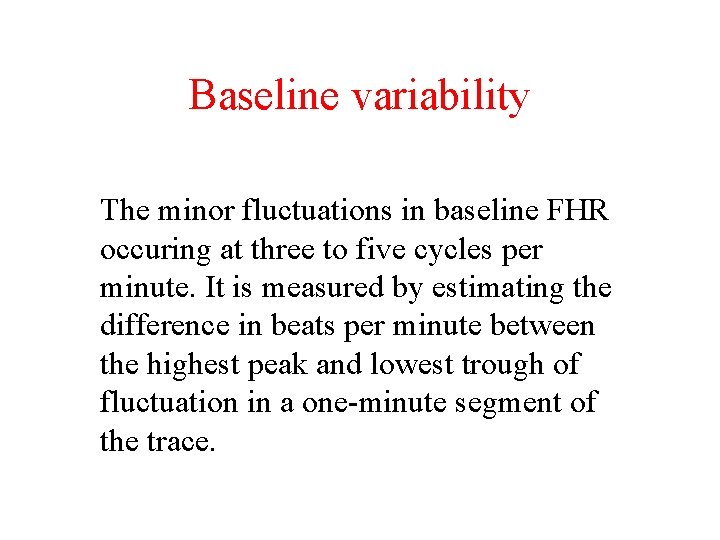

Baseline variability The minor fluctuations in baseline FHR occuring at three to five cycles per minute. It is measured by estimating the difference in beats per minute between the highest peak and lowest trough of fluctuation in a one-minute segment of the trace.

FHR Variability Absent variability = Amplitude range undetectable Minimal = < 5 BPM Moderate = 6 to 25 BPM Marked = > 25 BPM